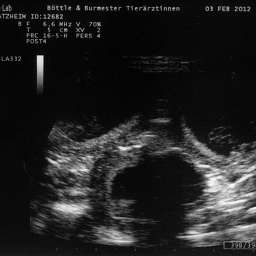

3.2.2012, 32.Tag: Der Ultraschalltermin ist vollbracht: Juhu, wir werden Eltern!!!

Aus Herzklopfen wurde Herzrasen und dann endlich, kurz vor der Herztablette, zeigte uns der Ultraschall 5 KLEINE WUNDER, gesunde Fruchthüllen, mit lebendigem Innenleben und pochendem Herzen. (...passte sehr gut zu unseren...)Wieviele es letztendlich werden, bleibt eine riesige Überraschung.

Bitteschön, ein kleines Filmchen mit dem Titel: "5 auf einen Streich, oder wie es in den Bauch hineinschallt, schallt es auch wieder hinaus."

4.2.2012, 33.Tag: Hier sind also die Fotos der kleinen Flauschmonster in ihren Höhlen.

Sucht Euch doch schon mal einen aus: